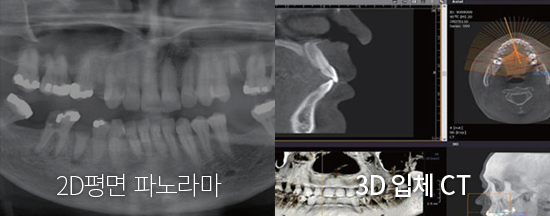

ÆÄ³ë¶ó¸¶ X-ray ÃÔ¿µÀ¸·Î´Â 2Â÷¿øÀûÀΠȯÀÚÀÇ Ä¡¾Æ »óŸ¸ È®ÀÎÇÒ ¼ö ÀÖ¾î ÀÓÇöõÆ® ½Ã¼ú °èȹÀ» Á¤È®È÷ ÇÒ ¼ö ¾ø½À´Ï´Ù. ÄÄÇ»ÅÍ ºÐ¼®À» Ȱ¿ëÇÑ ÀÓÇöõÆ®´Â ÃÖ÷´Ü µðÁöÅÐ ¹æ½ÄÀ¸·Î 3Â÷¿ø CT ÃÔ¿µÀ» ÅëÇØ ȯÀÚÀÇ °ñÁ¶Á÷, ÁÖº¯Ä¡¾Æ¿ÍÀÇ °Å¸®, °¢µµ, ½Å°æ À§Ä¡ µîÀÇ Á¤º¸¸¦ ÅëÇØ Á¤È®ÇÑ ½Ã¼ú °èȹÀÌ °¡´ÉÇÕ´Ï´Ù.